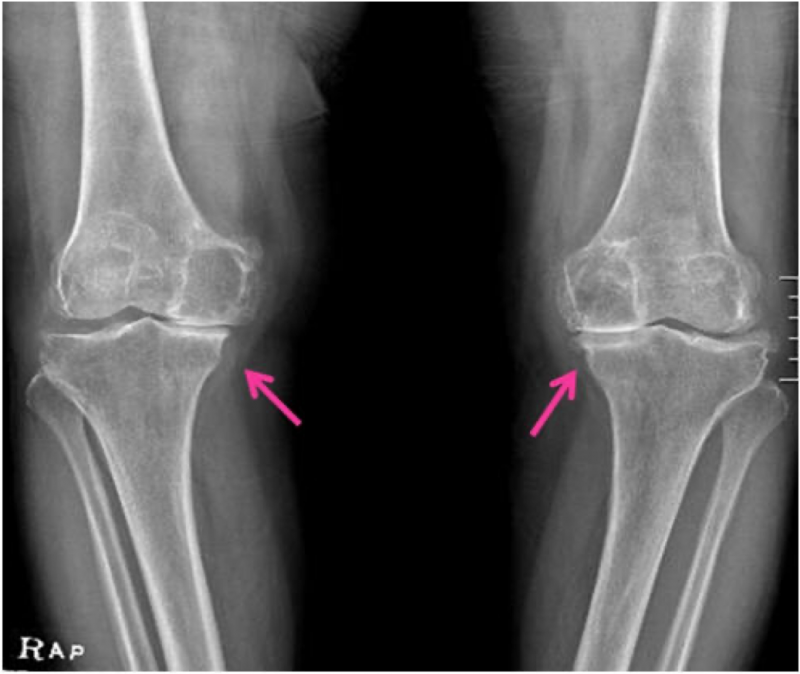

X-선 검사는 관절염이 있는 무릎에서 대부분의 경우 관절간격의 감소를 관찰할 수 있습니다.